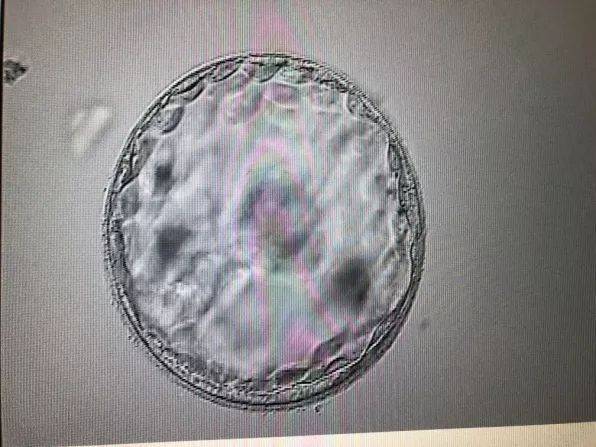

- 青岛试管婴儿取卵科普06-01

- 青岛试管婴儿攻略:科普06-01